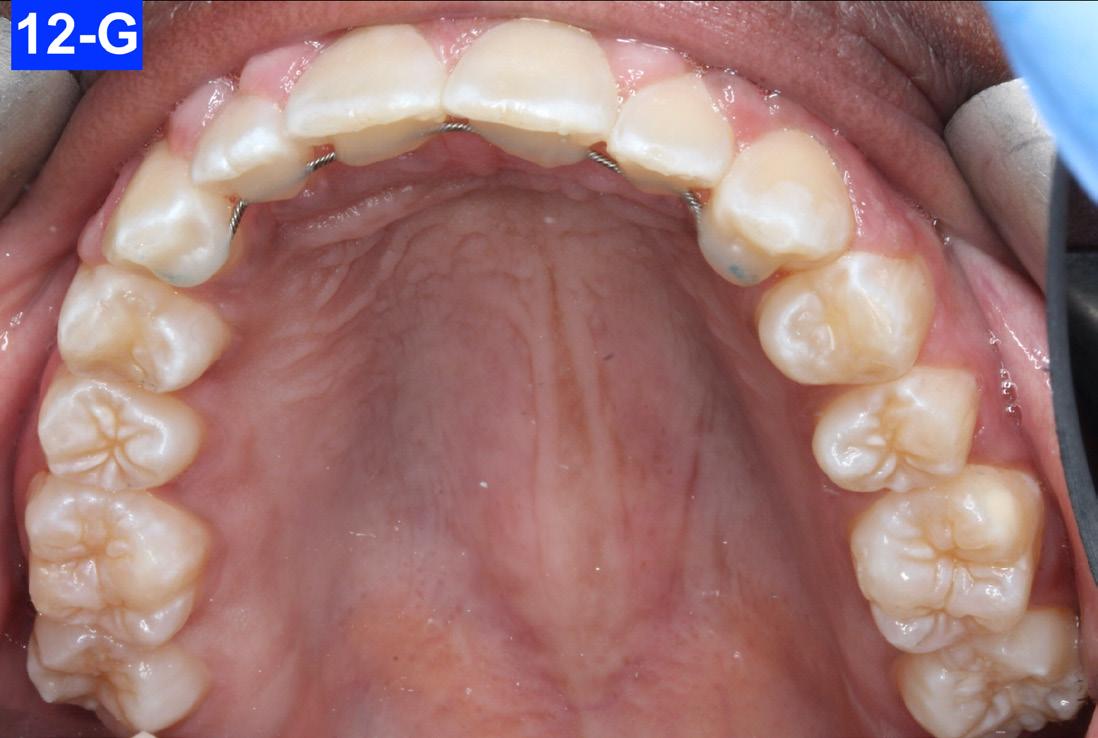

Figures 12-A to 12-M show the post-treatment images at the time of insertion of the retainers. We had an opportunity to evaluate the patient’s occlusion three years post-treatment. Compared to the initial post treatment evaluation, it was noted that the occlusion had settled into an even more stable position after three years.

Fig. 12-G: Post-treatment, MX occlusal view